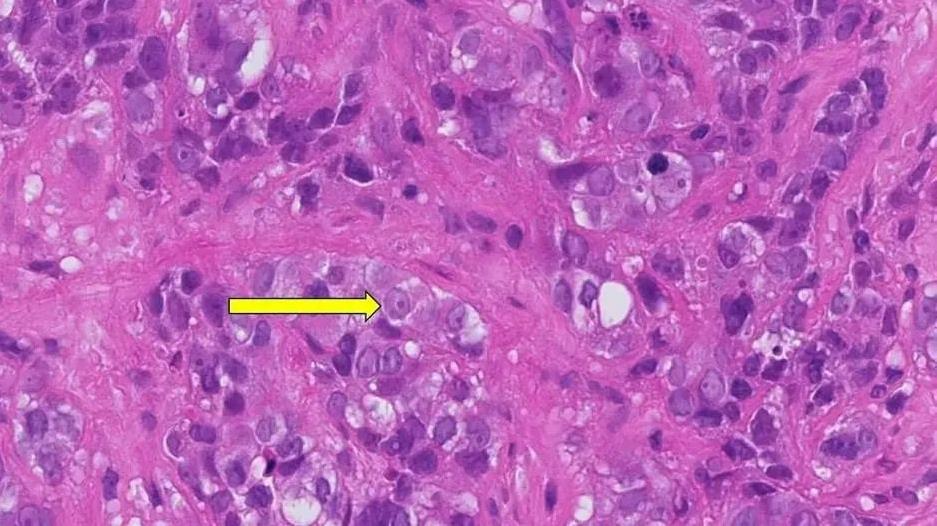

图1 无TIL细胞患者的肿瘤组织病理切片分析

▲图源“Mayo Clinic Cancer Center”,版权归原作者所有,如无意中侵犯了知识产权,请联系我们删除

注:上图为患者肿瘤组织病理切片,其内未见TIL细胞等免疫细胞。因此,患者的免疫系统无法攻击癌细胞(黄色箭头)。此类患者的复发风险较高,尤其是在没有化疗的情况下。